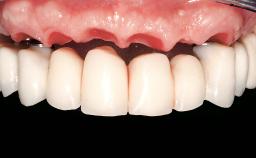

Immediate Loading of Eight Implants in the Maxilla and Six Implants in the Mandible and Final Restoration with Three-Unit and Four-Unit FDPs

Prosthesis Type FDP

Prosthodontic SAC classification

SAC Level Complex

Defining Characteristics Fully edentulous upper jaw to be rehabilitated with an implant-borne fixed dental prosthesis

Loading Protocol Immediate

Esthetic Risk High